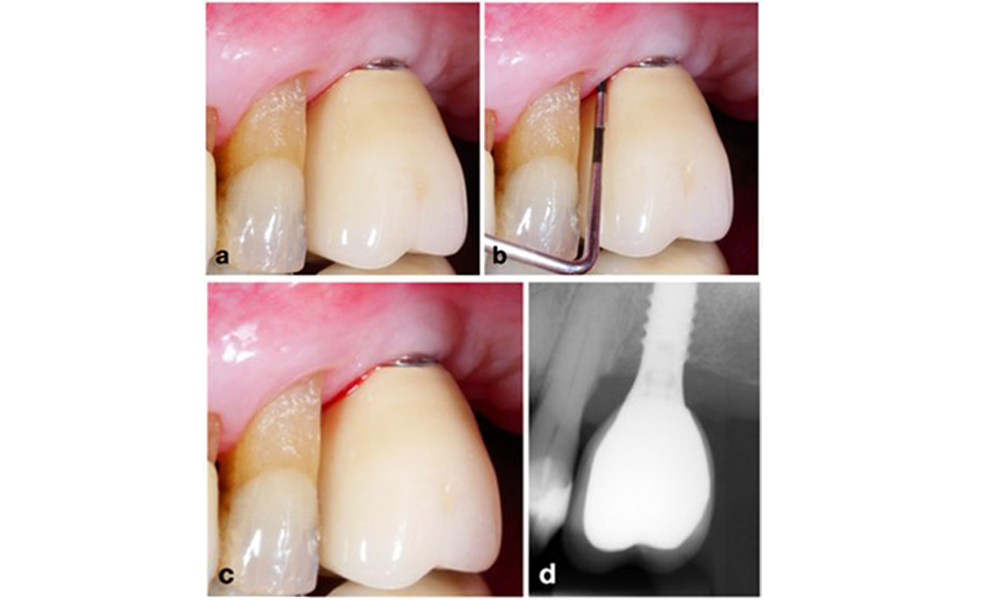

A Mnemonic Approach to Radiographic Precision

To achieve consistent and comparable radiographs over time without overlapping implant-threads, a simple mnemonic rule can be followed: “right blur, raise beam & left blur, lower beam – RBRB/LBLB” (see figure 3 adapted from Schropp et al. 2012).

For optimal intraoral radiographs of dental implants, follow this mnemonic rule: If the right side of the implant appears blurry on the peri-apical x-ray, raise the beam (i.e., directed more towards the ceiling) (a); if the left side appears blurry, lower the beam (i.e., directed more towards the floor) (b). This rule applies regardless of implant position in the upper or lower jaw. Example: Blurry threads on implants at positions 14 and 16, mostly at their right side, (c) were corrected by raising the beam by about 15 degree, resulting in a clear image showing bone-to-implant contact (d).

Figure 3. For optimal intraoral radiographs of dental implants, follow this mnemonic rule: If the right side of the implant appears blurry on the peri-apical x-ray, raise the beam (i.e., directed more towards the ceiling) (a); if the left side appears blurry, lower the beam (i.e., directed more towards the floor) (b). This rule applies regardless of implant position in the upper or lower jaw. Example: Blurry threads on implants at positions 14 and 16, mostly at their right side, (c) were corrected by raising the beam by about 15 degree, resulting in a clear image showing bone-to-implant contact (d).